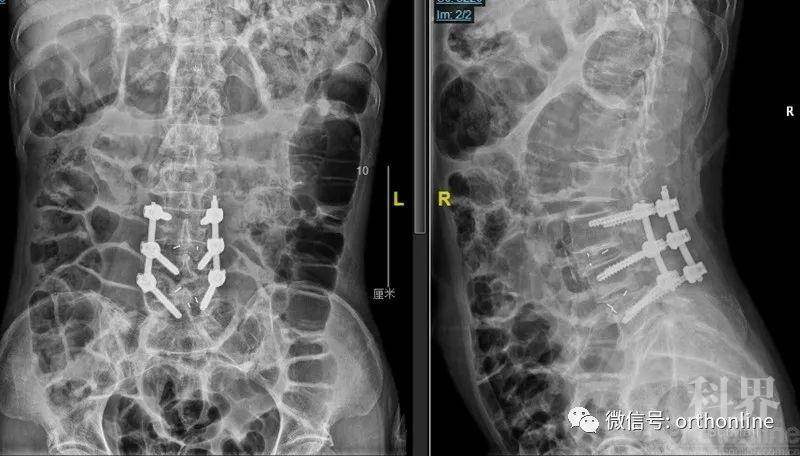

怎么看腰椎管狭窄图片,腰椎管狭窄手术图片

腰椎管狭窄手术图片

腰椎管狭窄手术